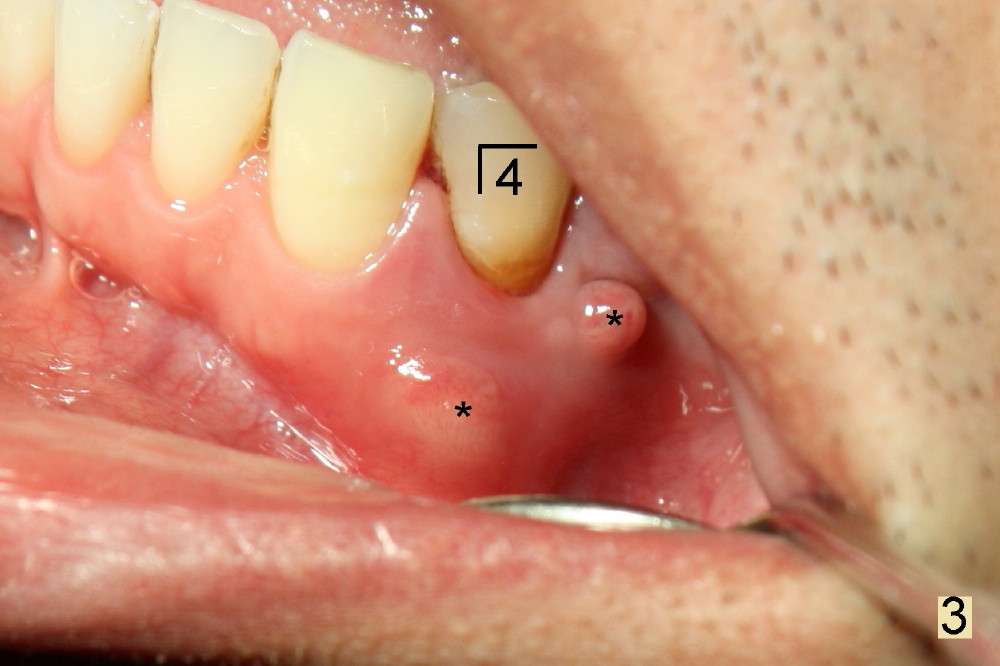

昨天(治疗后五年)左下第一双尖牙根部红肿(图三*),根尖片显示根裂(图四),阴影累及第二双尖牙植牙和尖牙根部(R)。由于发现突然,病人和家属不同意立即治疗,他们要等到病人下次放假才接受治疗,而我们心急如火,害怕炎症破坏植牙。如果条件允许的话,拔牙后即刻植牙(直径大些,长些,补偿巨大骨质缺损),目前抗菌素治疗,最好拔牙前再使用抗菌素一到两天。